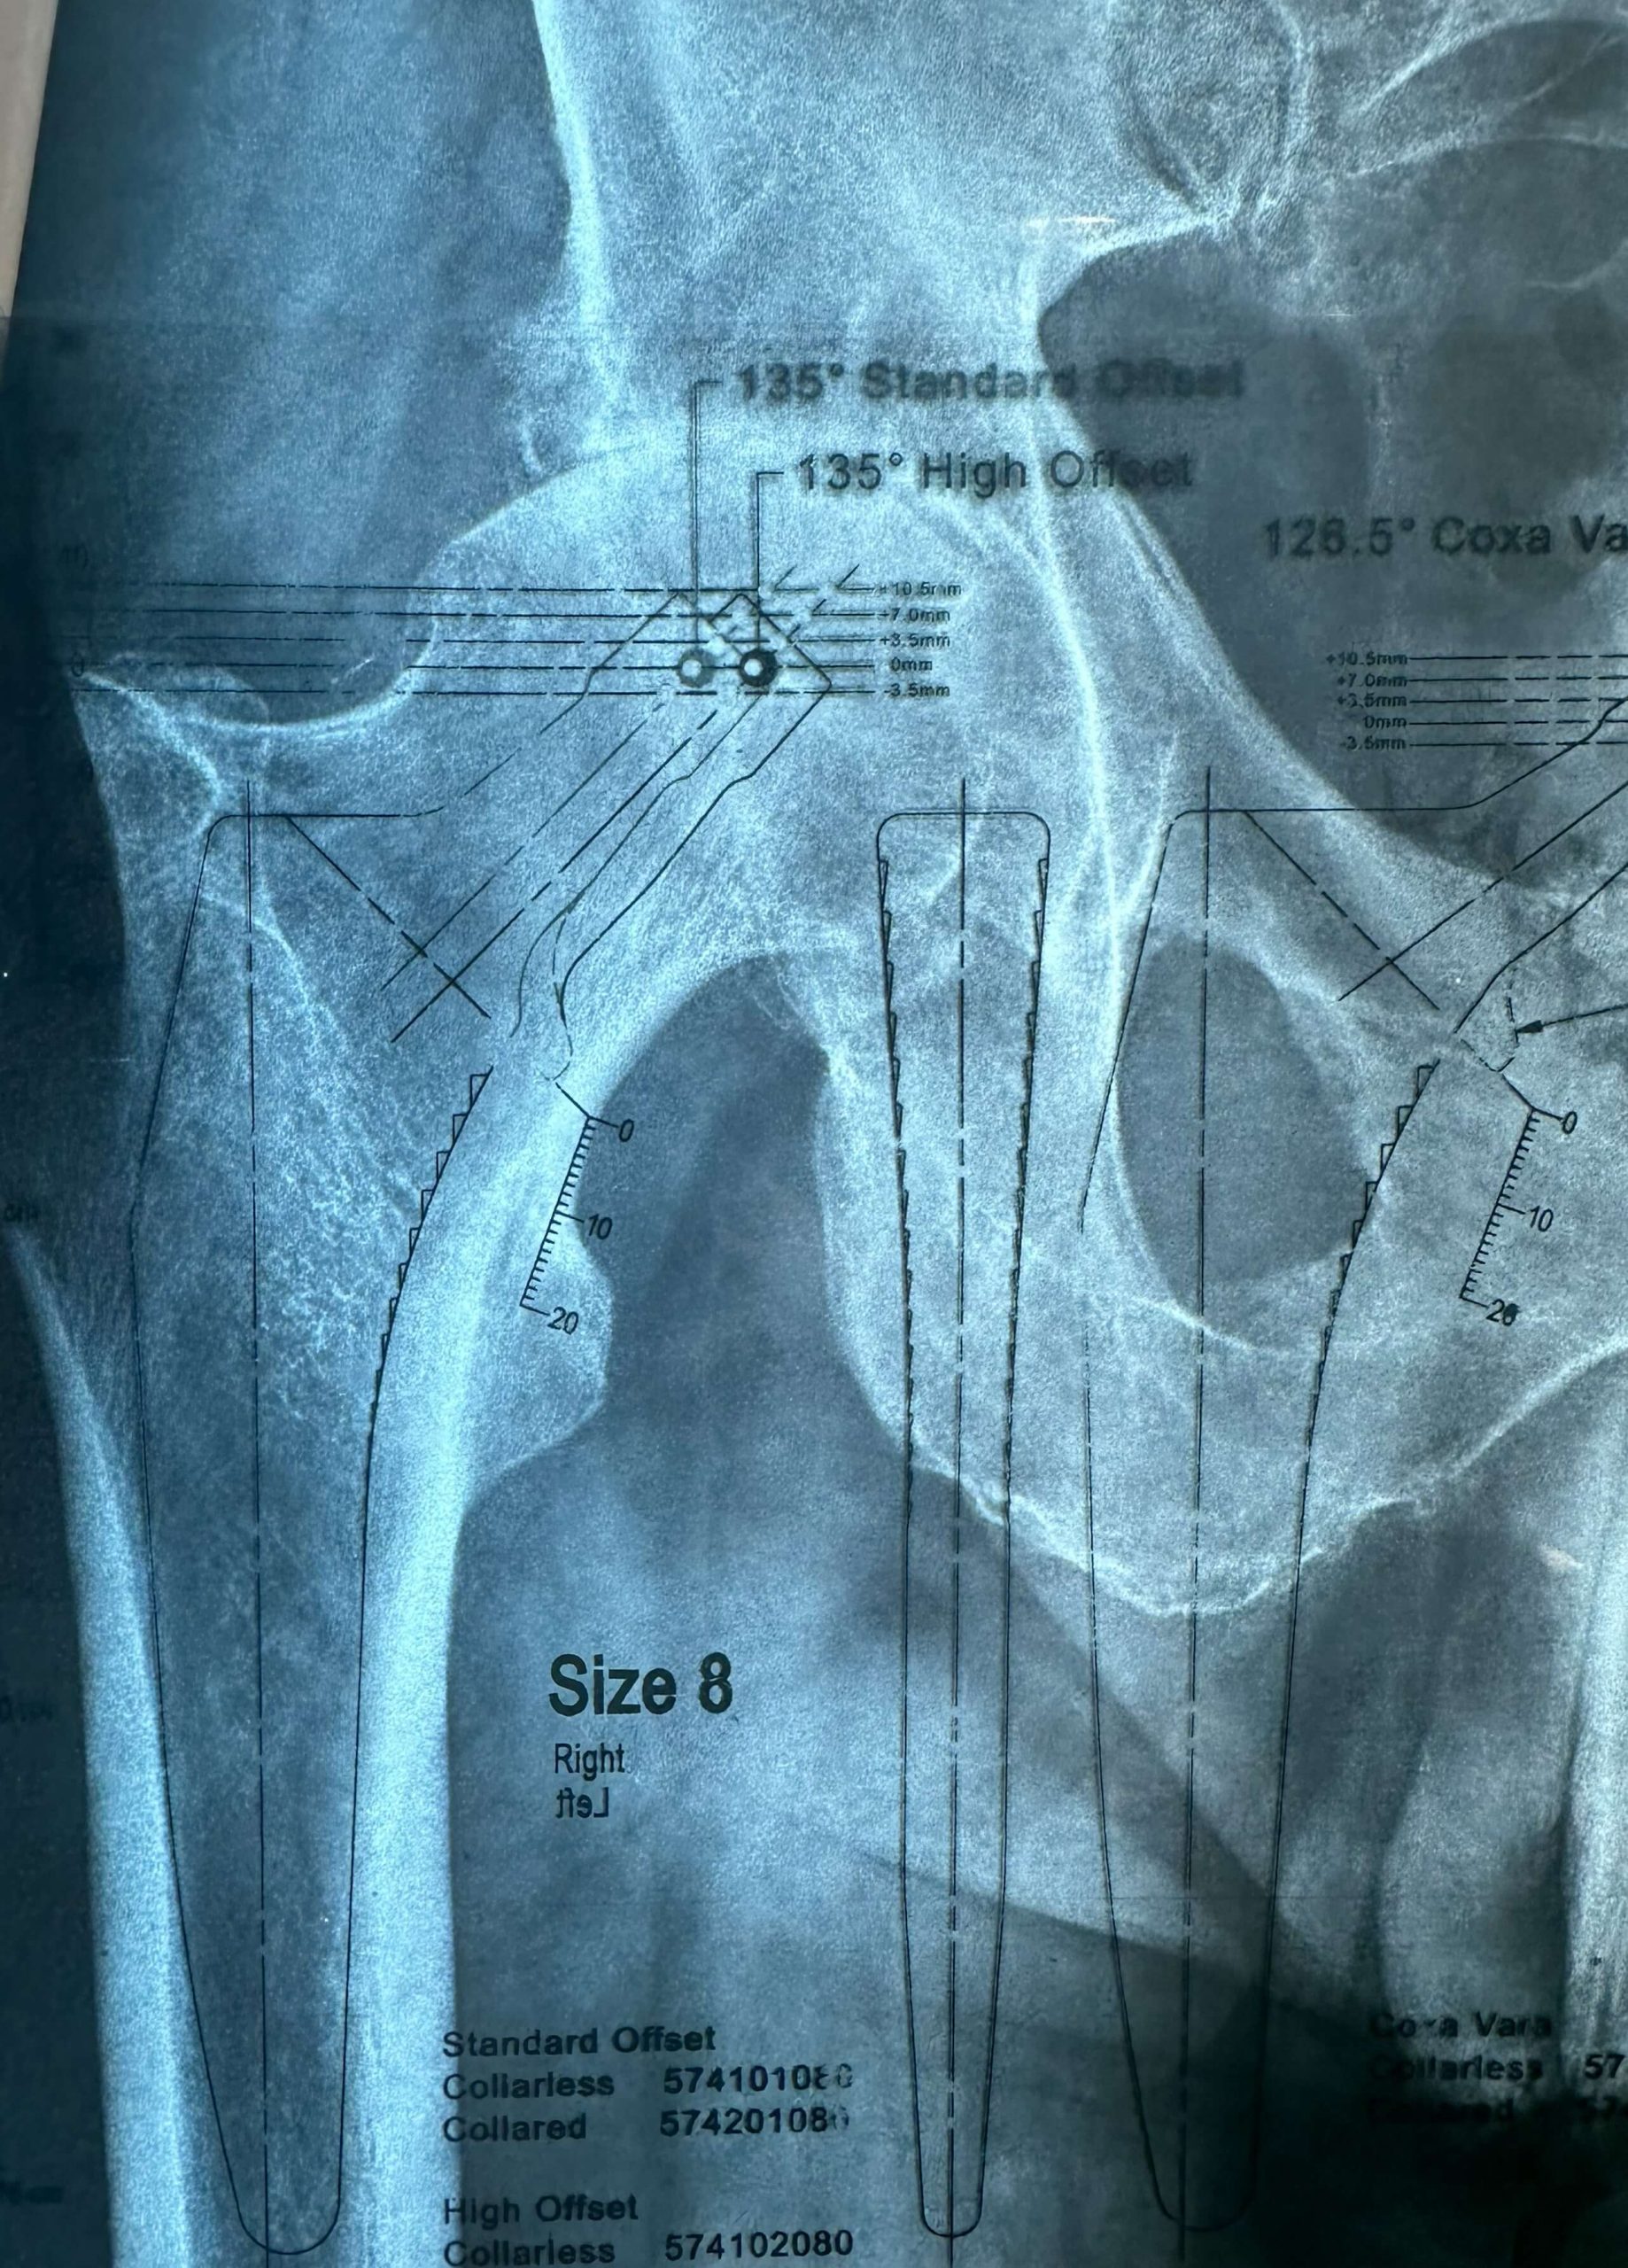

Προεγχειρητικός σχεδιασμός για την ακριβής επιλογή του τύπου και του μεγέθους του εμφυτεύματος.